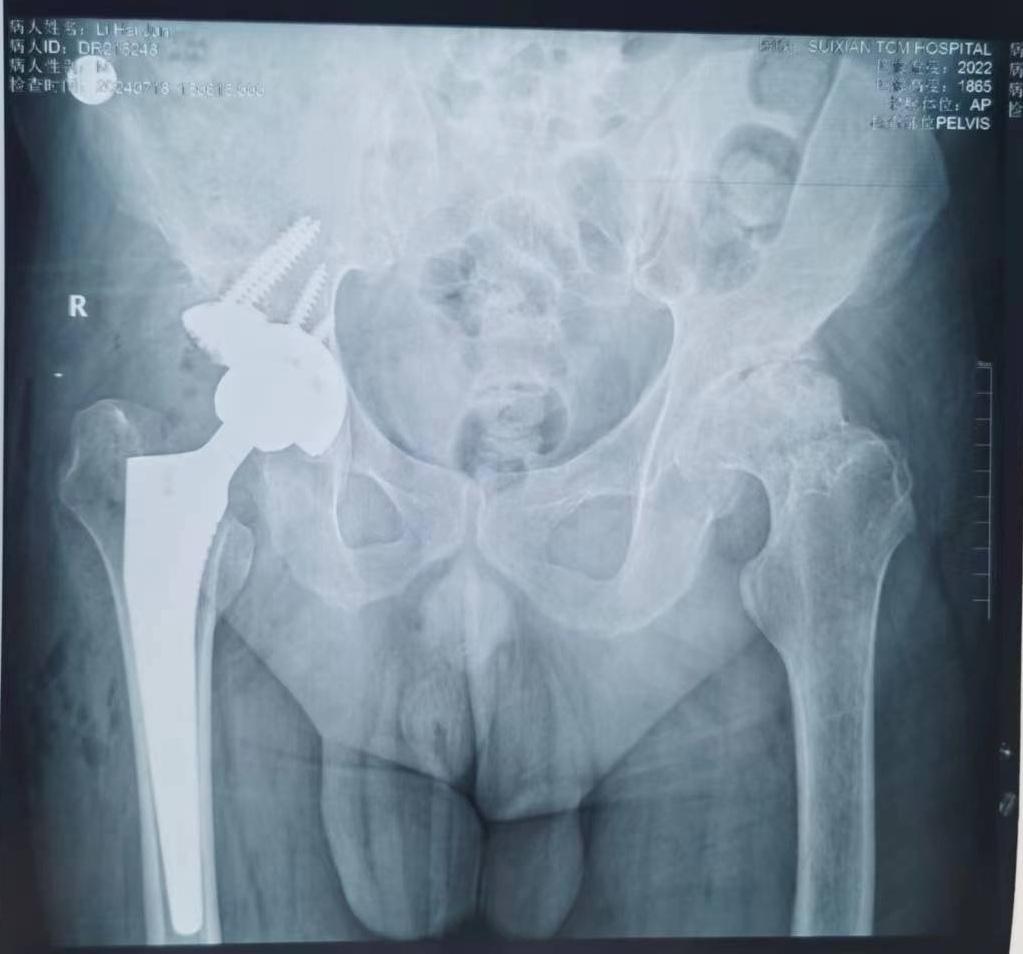

DDH髋关节置换。DDH高脱,术前短4cm,术后下肢等长,二期行对侧置换时还得注意下肢长度问题。用完美的功能恢复报答患者的信任🌹